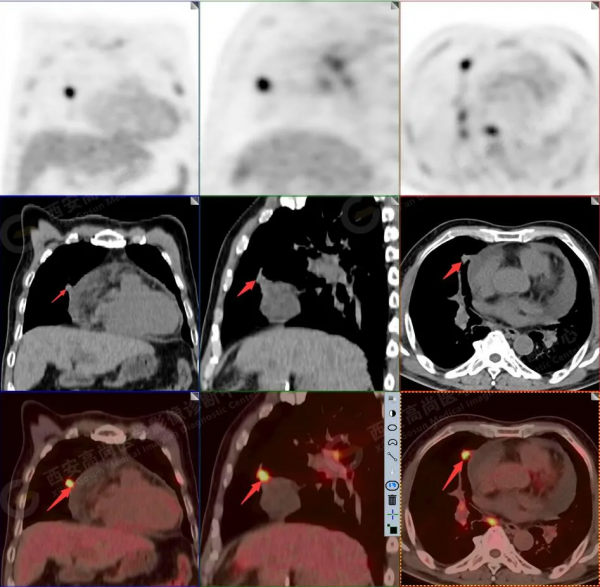

1.以下為肺內原發灶

1.右肺下葉後基底段軟組織結節(約1.5cm×1.2cm),與相鄰後胸膜分界不清,呈FDG代謝異常增高,結合病理,符合肺腺癌伴鄰近胸膜侵犯。

2.雙肺多發高密度小結節灶(最大徑約0.7cm),部分較大結節呈FDG代謝略增高,均考慮為轉移性病變。

3.右側肺門、縱隔(1L、1R、3A、4、6、7組)及雙側鎖骨上多發腫大淋巴結,呈不同程度FDG代謝異常增高,考慮為淋巴結轉移。

4.右後胸膜輕度增厚,形成多個條狀軟組織病變,呈FDG代謝輕度異常增高,考慮為轉移性病變;右側胸腔微量積液。

5.腰4椎體左側緣溶骨性骨質破壞,FDG代謝異常增高,考慮骨轉移瘤。

6.肝內小結節,考慮轉移可能性大,建議MR增強掃描。

以上病變符合:T4N3M1c,ⅣB期(UICC/AJCC,2018年第8版肺癌TNM分期)。